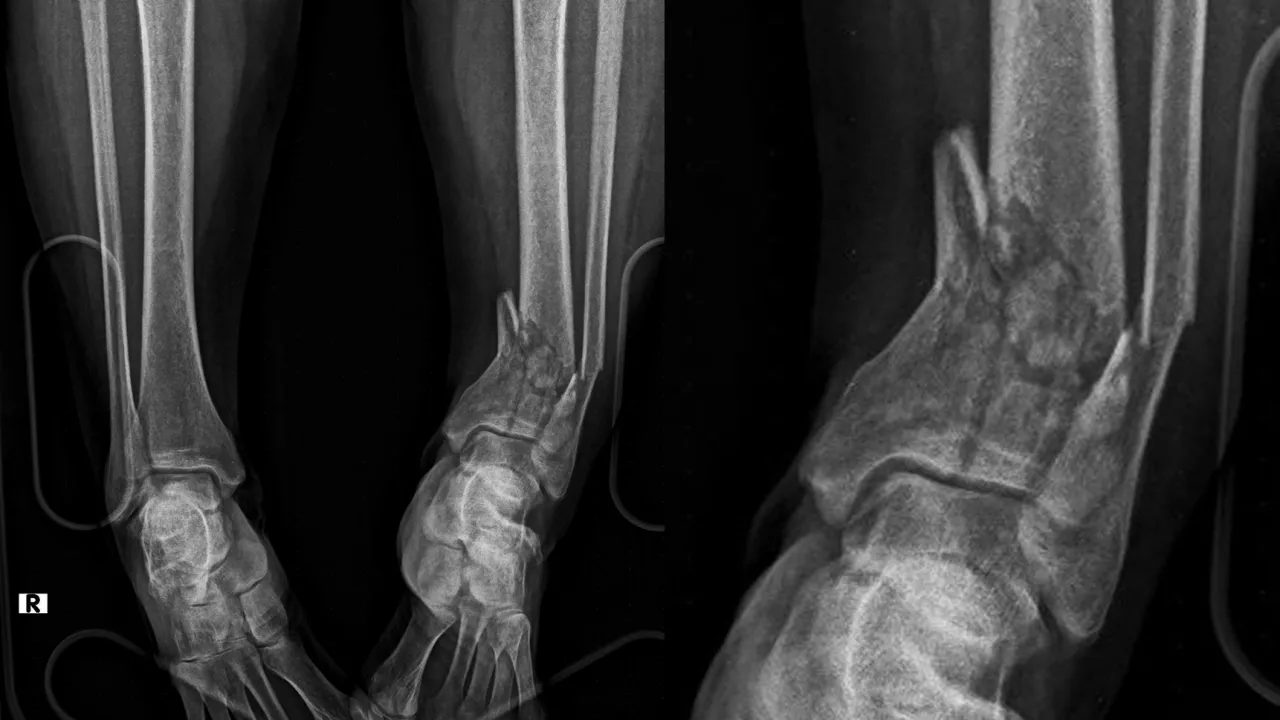

Travmalar, günlük yaşamda en sık karşılaşılan acil durumlardan biridir. Trafik kazaları, yüksekten düşmeler, spor yaralanmaları veya iş kazaları sonucu oluşan kırıklar, hızlı ve doğru müdahale edilmediğinde kalıcı sakatlıklara yol açabilir. Travma sonrası kırık cerrahisi, hastaların hayatını kurtaran ve fonksiyonel iyileşmelerini sağlayan en kritik tedavi alanlarından biridir. Kırık cerrahisini yapmayan ortopedist yoktur. Ancak burada yumuşak dokuya saygı gösterme ve bağların korunması, kırık tedavisi sonrasında kısa ve uzun vadede sonuçları etkileyen önemli faktördür.

Travma sonrası kırık cerrahisi, sadece bir kemik onarımı değil; hastanın yeniden ayağa kalkması, günlük hayatına dönmesi ve yaşam kalitesini geri kazanmasıdır. Modern görüntüleme teknikleri, güncel cerrahi yöntemler ve 7/24 acil müdahale sayesinde kırık tedavisinde yüksek başarı elde edilmektedir.

Kırık cerrahisindeki 15 yıllık tecrübemiz ve ekibimiz ile başta kalça kırıkları olmak üzere İzmir'de femur, tibia, ayak bileği kırıklarında ve humerus, dirsek kırıklarında hızlı ve deneyimli cerrahi tedavi sunuyoruz.

"Travma sonrası kırık cerrahisi: Kalça, ayak bileği, el bileği ve pelvis kırıklarında 7/24 acil cerrahi müdahale ile hızlı ve güvenli tedavi. İzmir’de uzman ortopedi ekibiyle hizmetinizde."